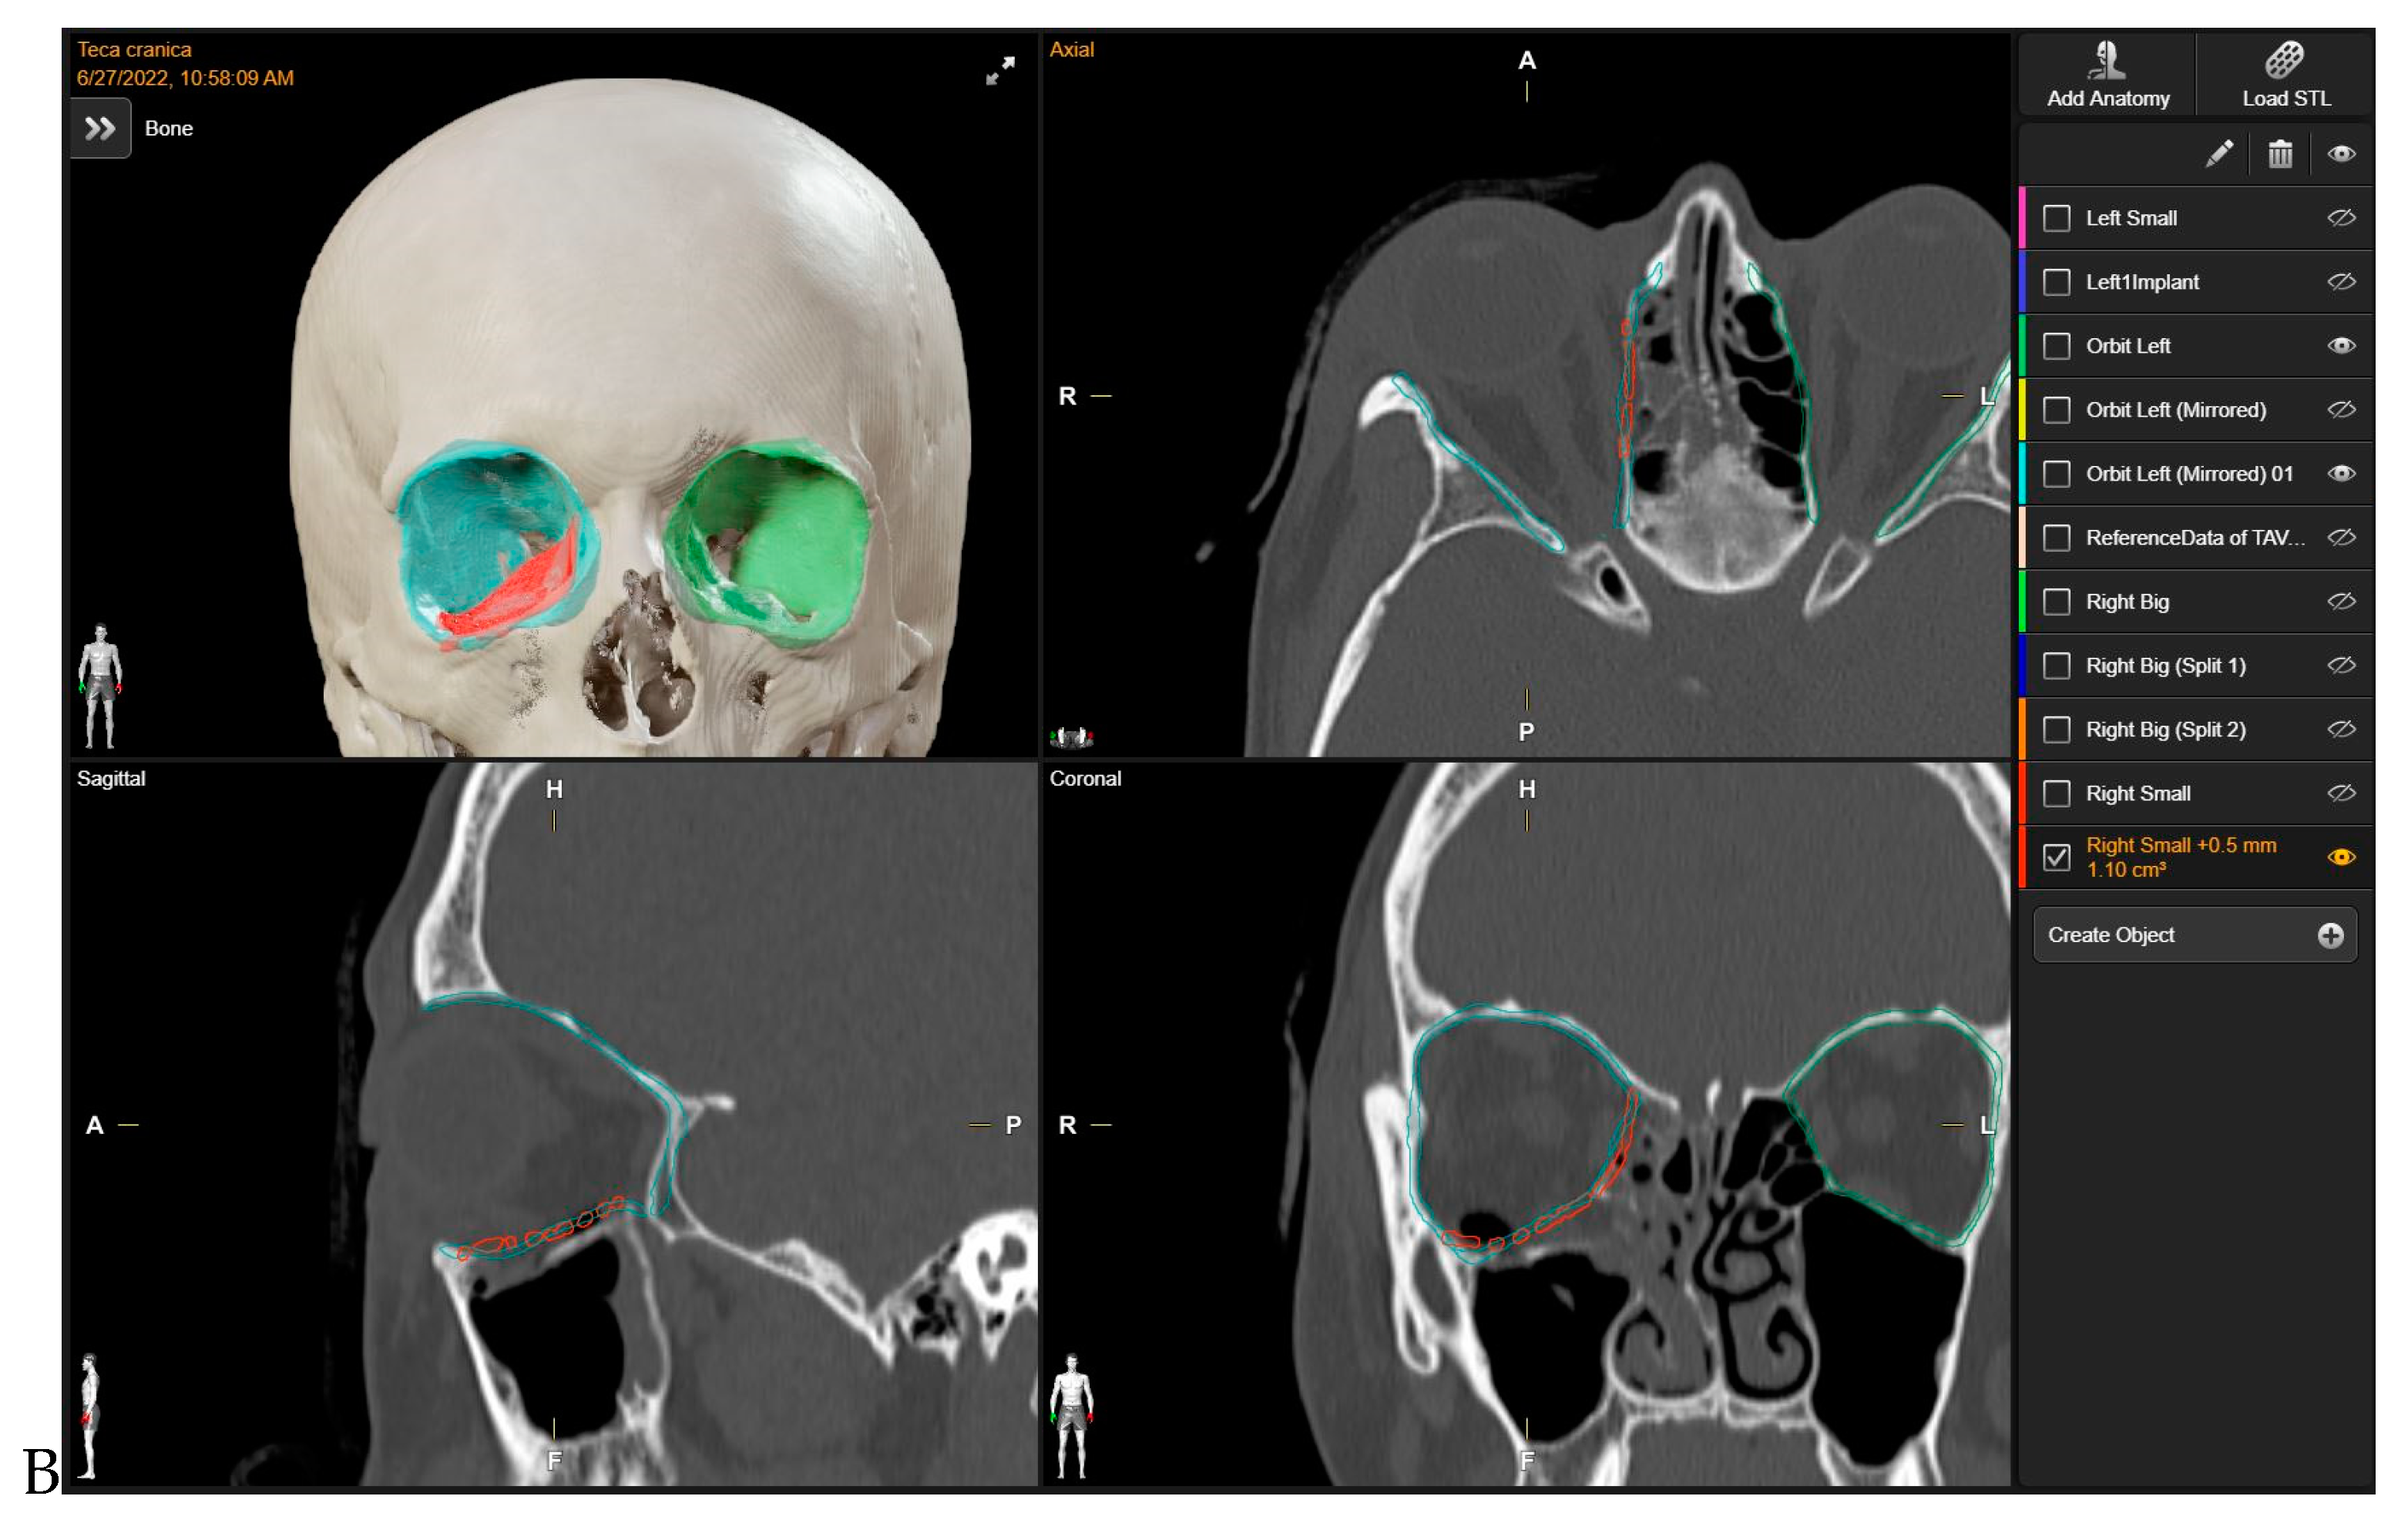

To evaluate the correspondence between the postoperative CT scan and the Virtual Surgical Planning (VSP), the process of overlaying postoperative CT scans onto preoperative planning images was executed through the “Image Fusion” tool within the software. “Brainlab Elements Contouring”, version 4.0 (Brainlab, Feldkirchen, Germany) (Figure 2), which creates an automatic alignment of preoperative images and postoperative CT scans. Subsequently, through visual inspection, areas where the boundaries of the superimposition were not perfectly aligned were carefully examined. In these regions, the mismatch between the postoperative CT plate and the simulated virtual positioning of the mesh was manually measured.

Orbital volume measurements of both the reconstructed and unaffected orbits were conducted using a dedicated tool for orbital volume measurement integrated into the software suite “Brainlab Elements Contouring”, version 4.0 (Brainlab, Feldkirchen, Germany). To maintain measurement integrity and minimize potential bias, we relied on the automatically generated volumes produced by the software. Given the precision and specialized functionality of this tool within the Brainlab portfolio, we considered the automatically generated volumes to be robust and indicative of the true orbital volumes. By calculating boundaries on presurgical CT scans, the software’s algorithms incorporate anatomical landmarks and contours, ensuring accurate delineation even in cases of anatomical variation or pathology, without the need for manual adjustments.

The volume of the unaffected contralateral orbit serves as a reference for comparison. Subsequently, the volume discrepancy between the reconstructed and contralateral orbits was computed (Figure 3).

Figure 2. The overlaying of postoperative CT scans onto preoperative planning images.

Figure 3. Post- operative Orbital Volume Measurements.